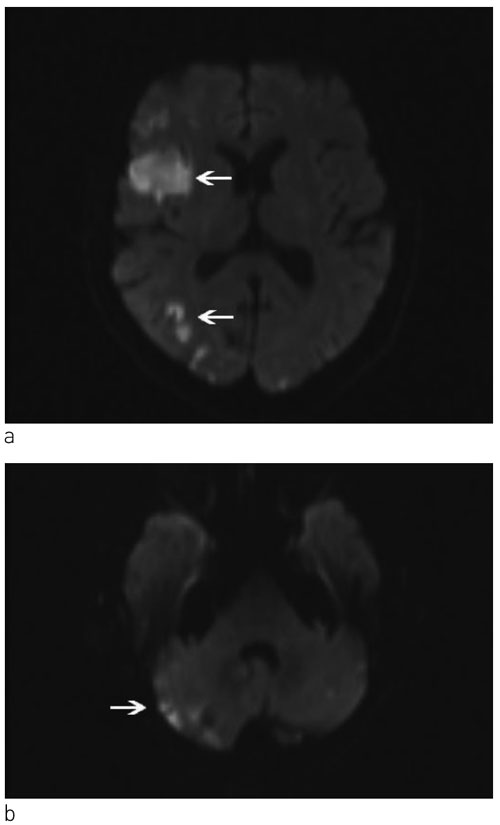

Operativ behandling av primærtumor i lungen ble vurdert, men til tross for kombinasjonsbehandling med dalteparin og acetylsalisylsyre fikk pasienten i påvente av operasjon akutt venstre hemiparalyse, forverring av kognitiv svikt og ble helt pleietrengende. Hun hadde D-dimer > 20 mg/l (normalt 0,00 – 0,50) og troponin-T 3722 ng/l (normalt < 15). MR av hjernen viste et stort infarkt i høyre a. cerebri medias forsyningsområde (fig 2). Pasienten ble tverrfaglig vurdert som inoperabel på grunn av et aggressivt forløp med raskt tilbakevendende og multiple organtromboser. Risikoen for nye tromboemboliske hendelser som følge av perioperativ seponering av antikoagulasjonsbehandling ble vurdert som høyere enn den mulige operative nytten. Hun ble utskrevet til sykehjem og fikk palliativ strålebehandling mot mediastinum og høyre fossa supraclavicularis på grunn av infiltrative lymfeknuter subcarinalt, pretrakealt og i øvre høyre mediastinum. Som komplikasjon til hjerneinfarktene utviklet hun epilepsi. Klopidogrel ble kombinert med dalteparin og acetylsalisylsyre på grunn av akutt hjerteinfarkt med ST-segmentelevasjon under denne innleggelsen. Til tross for aggressiv antikoagulasjonsbehandling rapporterte datteren senere om en forbigående episode hvor det paretiske venstre beinet ble smertefullt, hvitt og kaldt, suspekt på perifer arteriell emboli. Ett år etter sykdomsdebut døde pasienten av hjerte- og lungesvikt betinget av betydelig tumorvekst. Autopsi ble ikke utført.